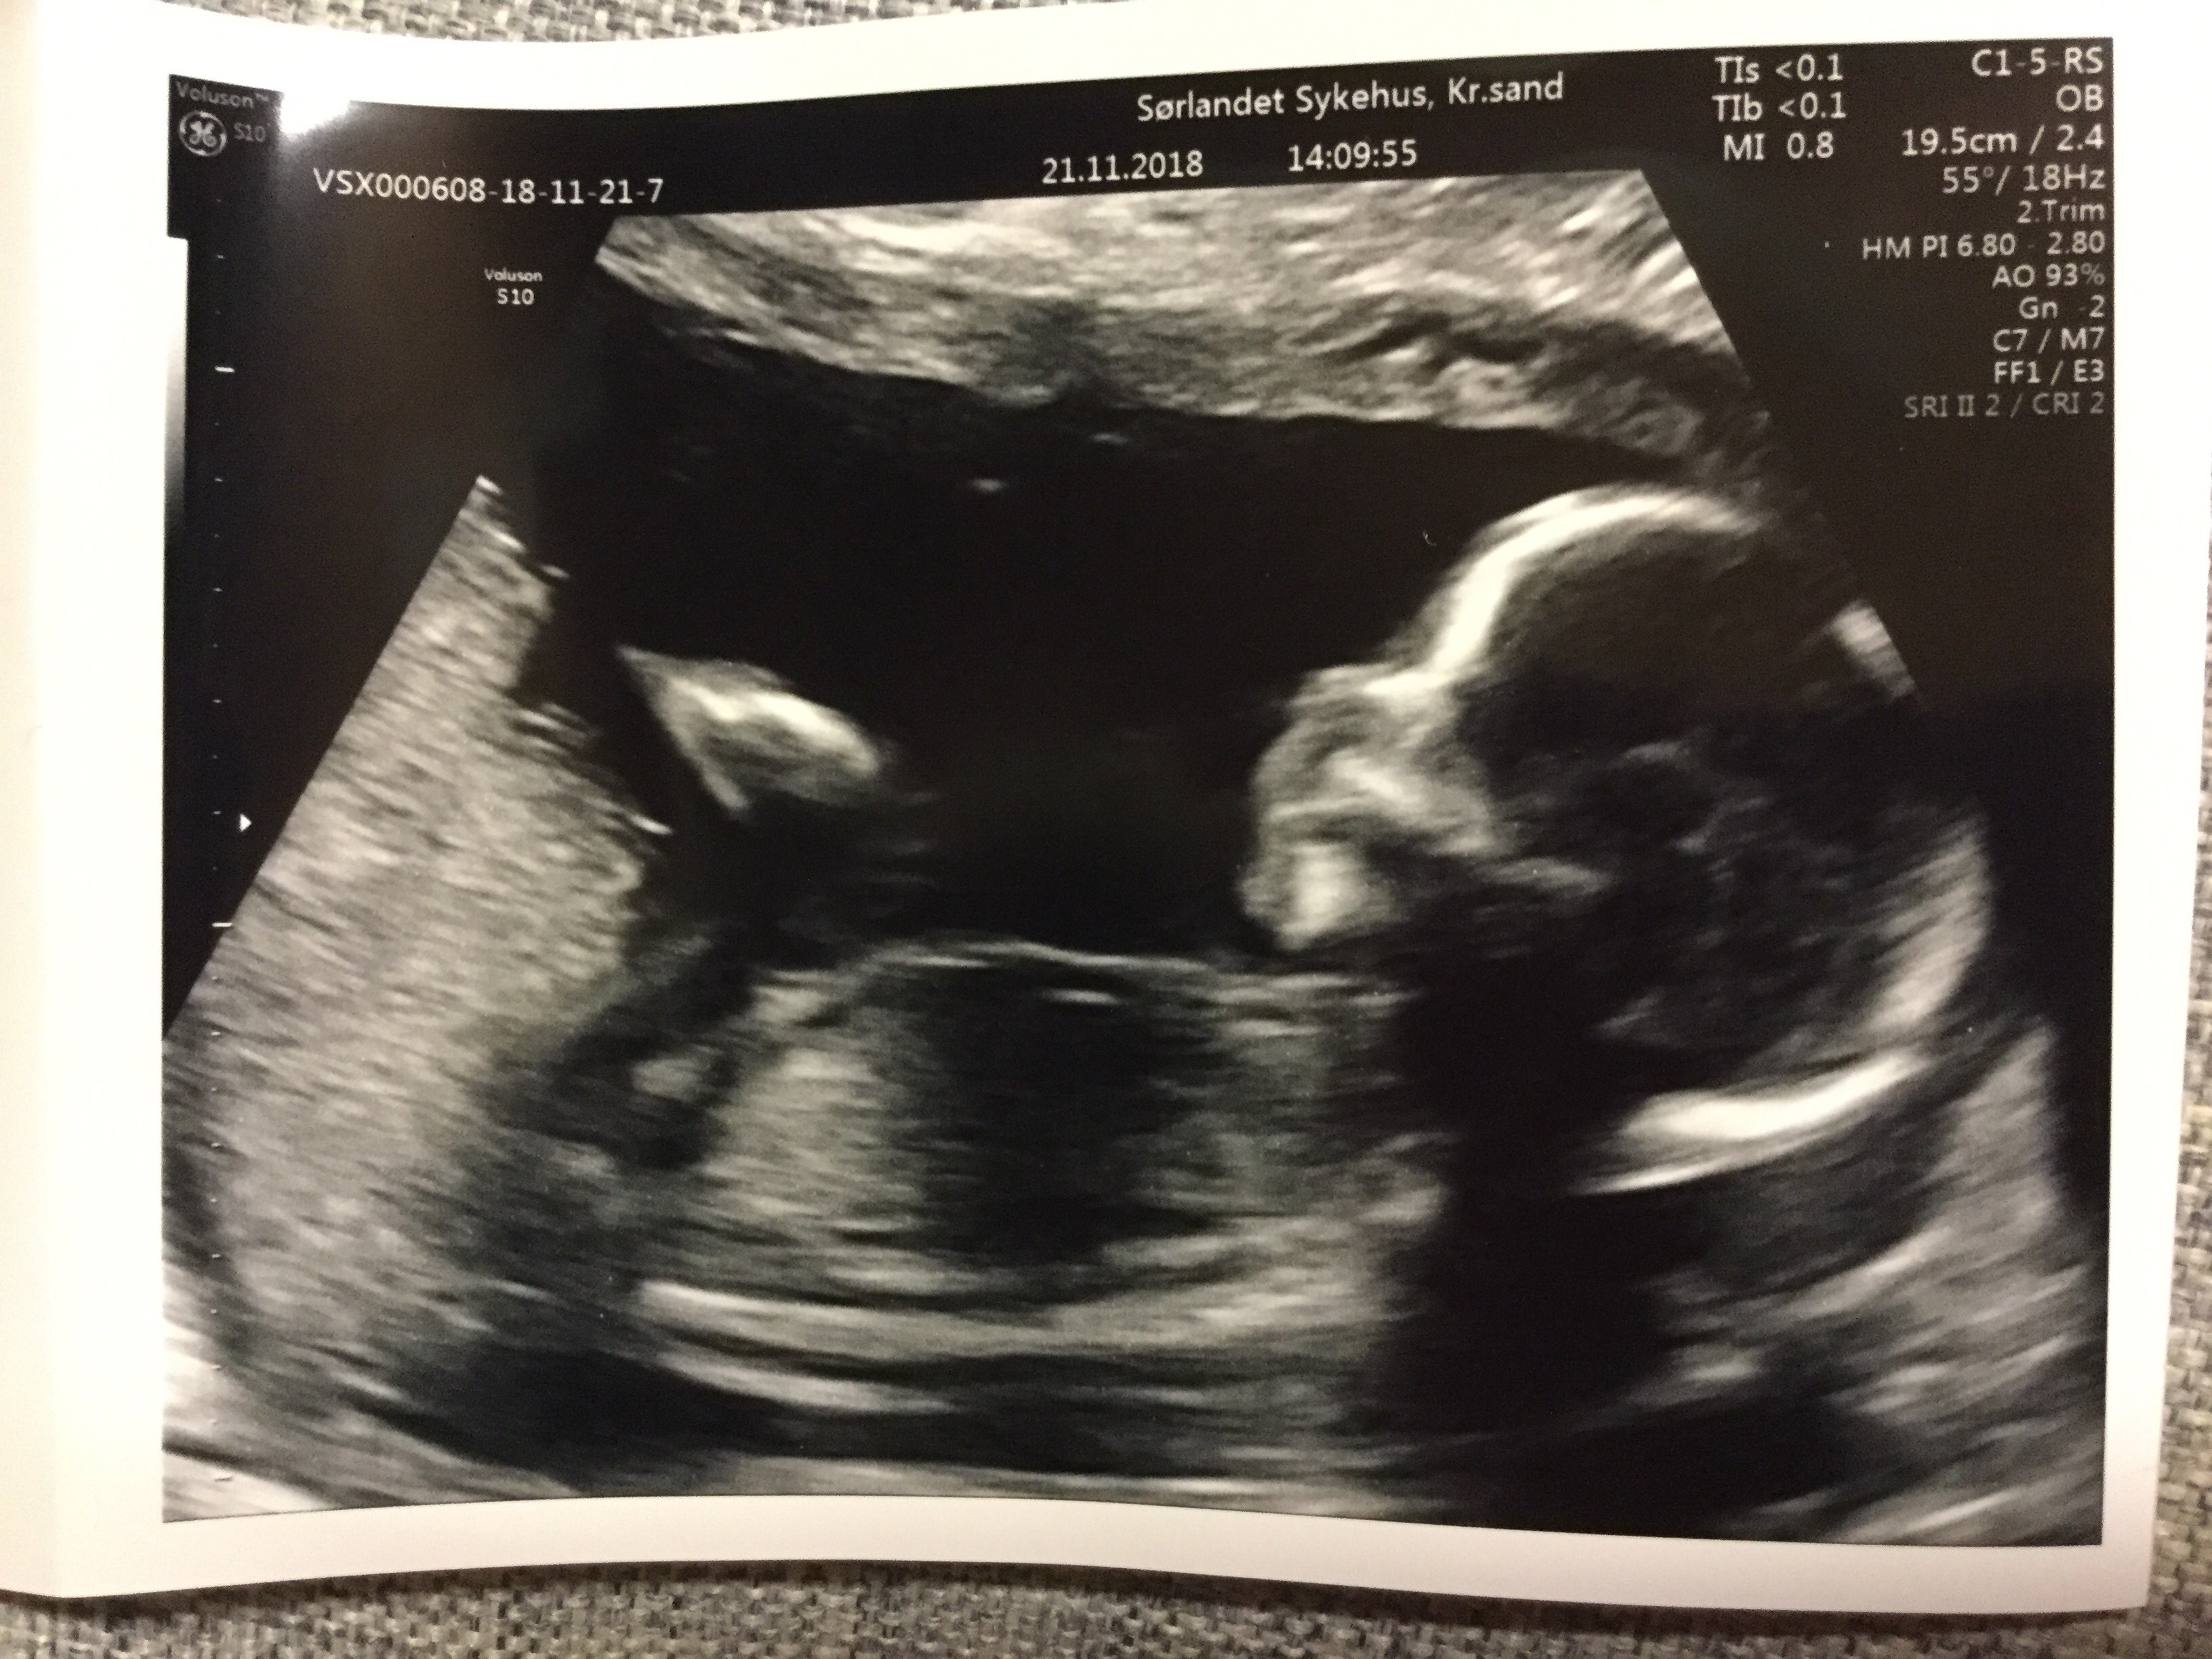

om 19+5

usg 20+2

Tętno: 161 u/min

Waga: 311g

Płeć: chłopiec

serduszko, przepona, płuca, żołądek, pęcherz, nerki, mózg w normie.

czaszka, kończyny, kręgosłup ok.

kość nosowa, fald karkowy, usta nos norma.

łożysko w dnie macicy, ściana przednia

kanał szyjki długości prawidłowej

prawidłowa ilość płynu owodniowego

pępowina trójnaczyniowa

maluszek wygląda na uśmiechniętego :)